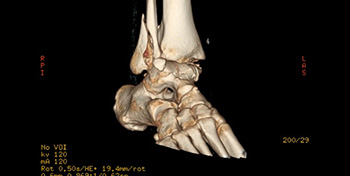

- Fractured ankle – 3D scan reconstruction showing ankle fracture